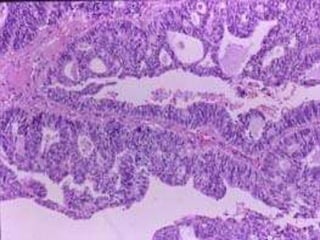

Adenoma pleomorfo

 Tumor más frec. de

glándulas salivales

 Predomina en parótida

 7% salivales menores

 En cav.oral: 50% de gl.

Salivales menores

 Cavidad oral: Paladar

 Crecimiento lento

 Masa firme, dolorosa no

ulcerada

 Sin cápsula

 4a. a 6a. década

 Pero a cualquier edad

Adenoma pleomorfo  Tumormás frec. de glándulas salivales  Predomina en parótida  7% salivales menores  En cav.oral: 50% de gl. Salivales menores  Cavidad oral: Paladar  Crecimiento lento  Masa firme, dolorosa no ulcerada  Sin cápsula  4a. a 6a. década  Pero a cualquier edad